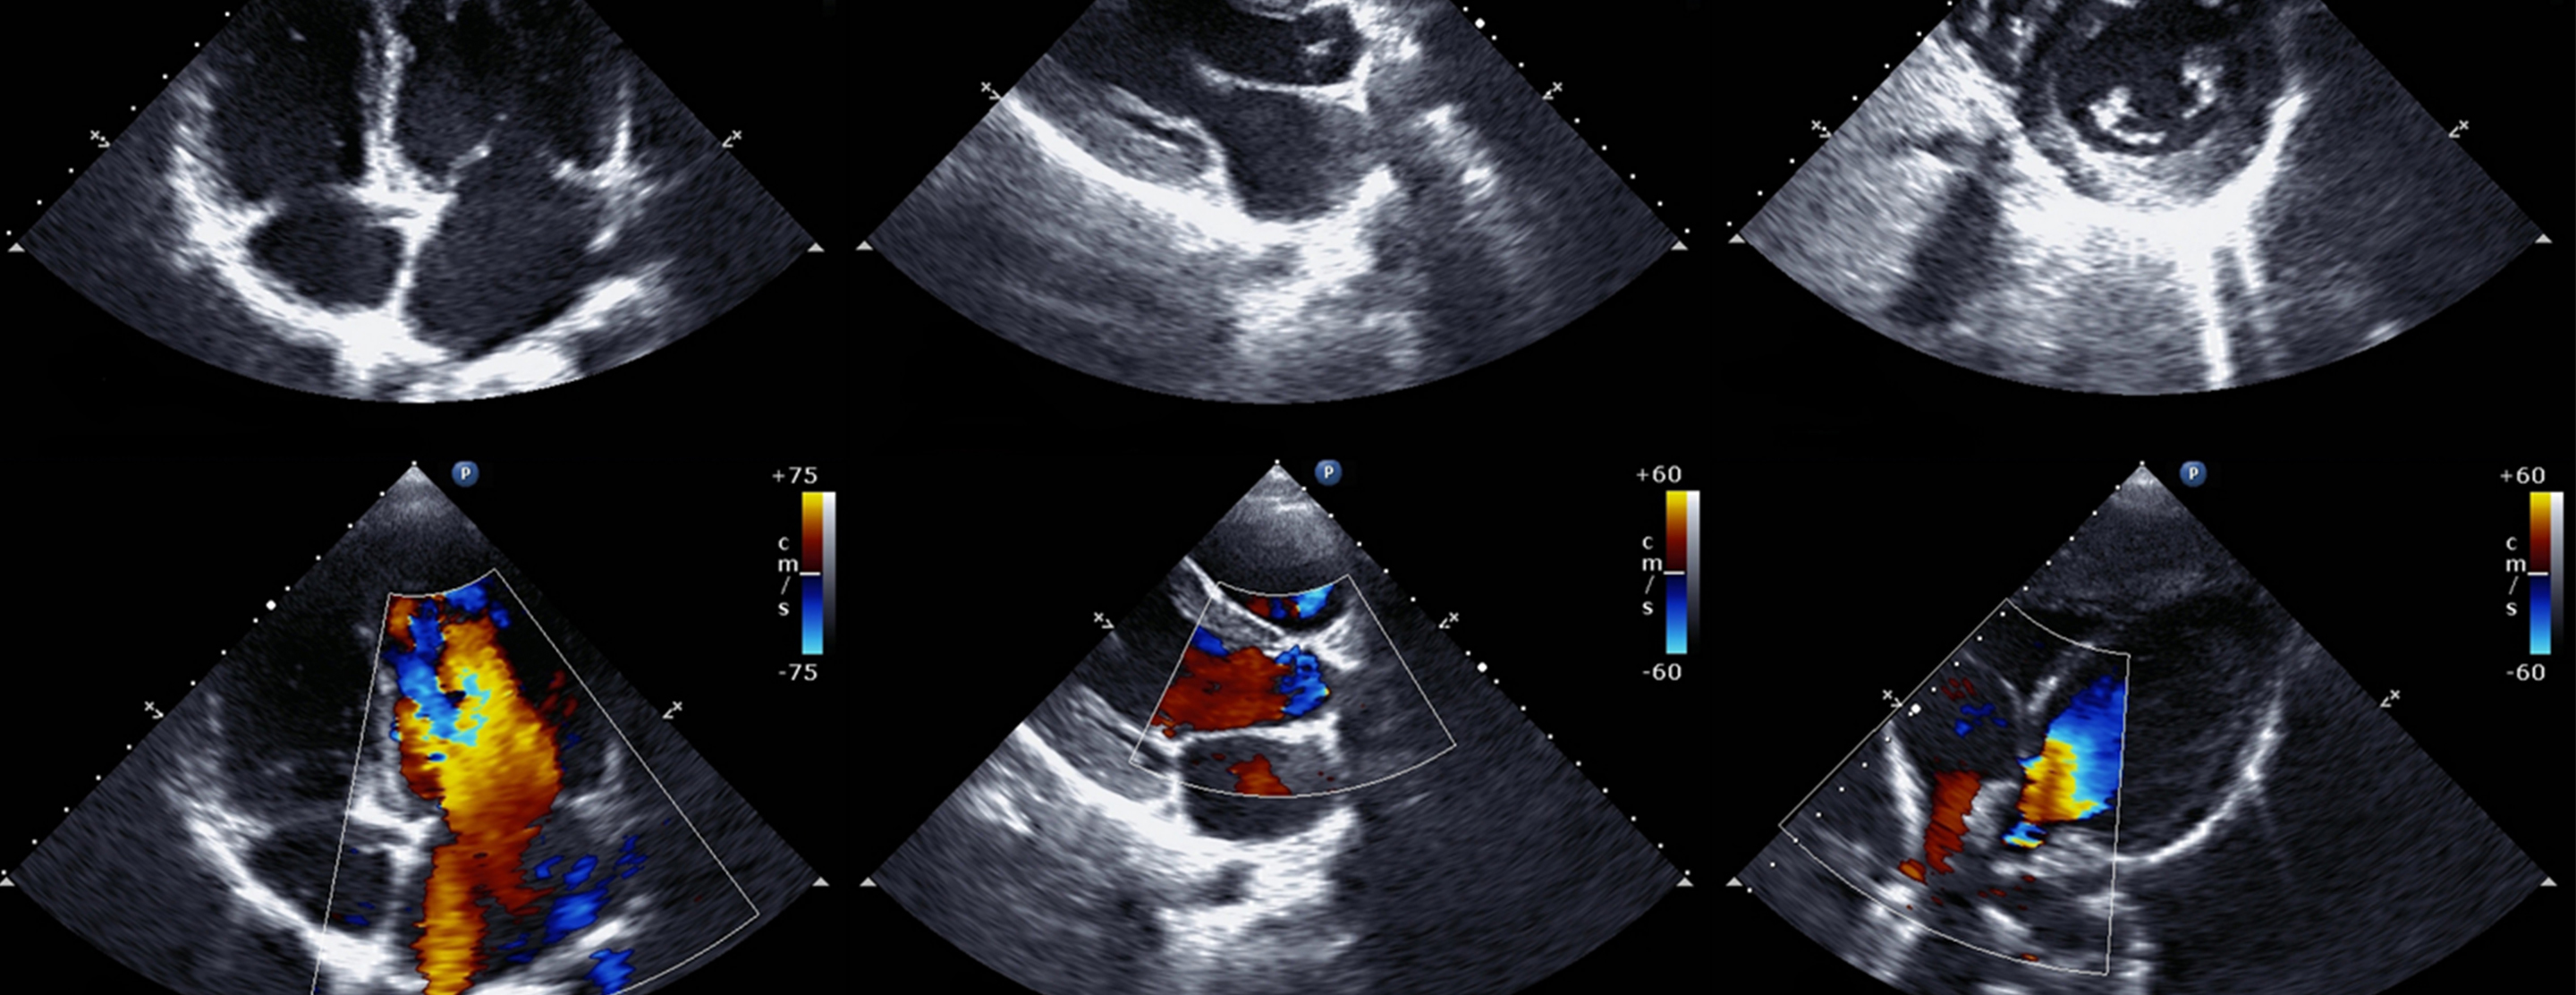

Có 4 kiểu siêu âm Doppler: Siêu âm doppler liên tục, siêu âm Doppler xung, siêu âm Doppler năng lượng, siêu âm Doppler màu. Trong quá trình siêu âm Doppler, đầu dò sẽ được đặt lên da của người được siêu âm và di chuyển trên vùng cơ thể cần kiểm tra. Đầu dò phát ra sóng âm dội lại các vật thể chuyển động. Các sóng âm phản xạ tạo ra hình ảnh chuyển động bên trong cơ thể người. Máy siêu âm sẽ tổng hợp và hiển thị trên màn hình dưới dạng các màu sắc, các dạng sóng phổ khác nhau hoặc tín hiệu âm thanh có thể nghe được.